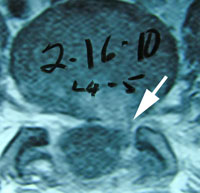

- Case Report: Cervical Spine Post-Surgery

Probably no area of chiropractic spinal manipulation is as challenged as treating the post-surgical patient who is the same, worse, or disenchanted with their surgical outcome. Certainly, the opportunity to treat the patient before surgical intervention is best. When confronted with this post-surgical patient, however, the chiropractic physician proceeds as if with a patient who has not had surgery. i.e. The chiropractor will proceed with the careful history and clinical examination to determine what is causing the pain. That cause may be within the surgical site or adjacent to it. In treating the post-surgical spine, fusion or no fusion is a dictator of care. If there is a fusion, spinal manipulation is given to adjacent levels of the spine to the fused area. If there is no fusion, the doctor carefully proceeds as if no surgery. Some motion may be possible within the spine depending on the surgical procedure performed. (11)

Let’s look at some factors of interest and importance to a patient seeking chiropractic care for their post-surgical spinal problem. (11)